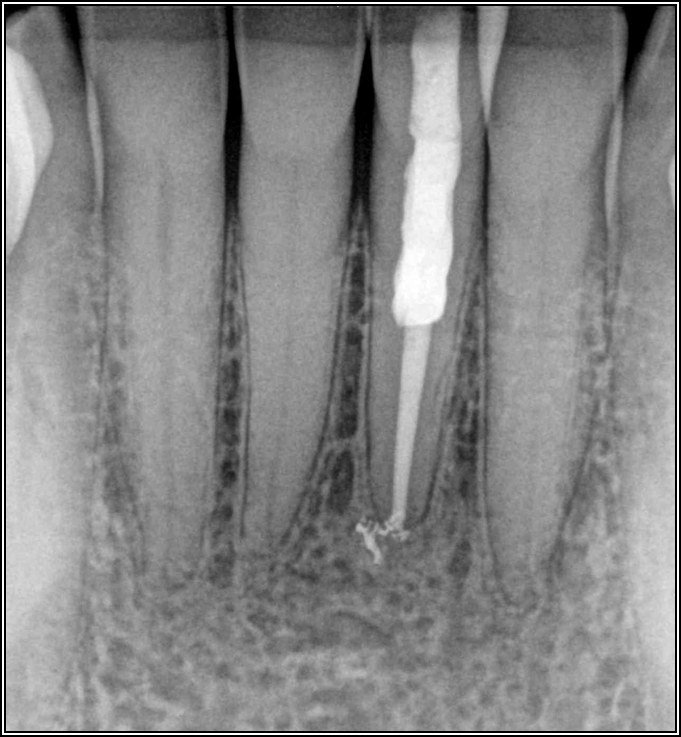

Fig 1. Limited access.

Figure 1

Root-Canal Access

Ultimately, the aim in endodontics is to preserve the tooth as long as possible for the patient. A clinician may want to do a root canal but must face realistic concerns, such as not having enough tooth.Figure 1 shows a case where the clinician was able to access four canals through a zirconium crown, with limited access. Generally, it is preferable to err on the side of opening larger and cleaning out well. If the access is too small, three problems arise: (1) clinicians may not clean effectively; (2) there is a greater chance of separation because there is not enough of a straight path, and (3) canals may be missed. Conversely, if clinicians open too large, they can destroy the tooth. There is a happy medium where the result is fine-tuned and engineered perfectly. Although the perfect result is not always possible or ideal, clinicians continue to strive for it. The best approach is to find the canals and then open them up under a microscope to get enough access. This gives the clinician whatever shape is needed for conservative access.